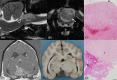

Results: No associations were found between clinicopathologic findings or survival and tumor type or grade. However, definitive treatments provided significantly (P = .03) improved median survival time (84 days; 95% confidence interval [CI], 45-190) compared to palliative treatment (26 days; 95% CI, 11-54). On magnetic resonance imaging (MRI), oligodendrogliomas were associated with smooth margins and T1-weighted hypointensity compared to astrocytomas (odds ratio [OR], 42.5; 95% CI, 2.42-744.97; P = .04; OR, 45.5; 95% CI, 5.78-333.33; P < .001, respectively) and undefined gliomas (OR, 84; 95% CI, 3.43-999.99; P = .02; OR, 32.3; 95% CI, 2.51-500.00; P = .008, respectively) and were more commonly in contact with the ventricles than astrocytomas (OR, 7.47; 95% CI, 1.03-53.95; P = .049). Tumor spread to neighboring brain structures was associated with high-grade glioma (OR, 6.02; 95% CI, 1.06-34.48; P = .04).

Conclusions and clinical importance: Dogs with gliomas have poor outcomes, but risk factors identified in survival analysis inform prognosis and the newly identified MRI characteristics could refine diagnosis of tumor type and grade.